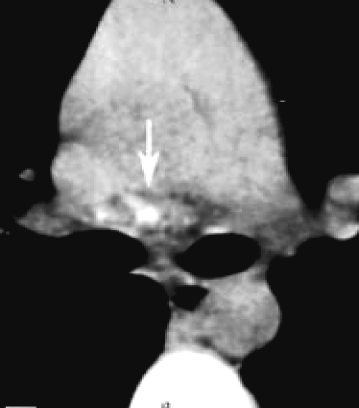

После инфицирования микобактериями туберкулёза в лимфатических узлах развивается гиперпластическая реакция с последующим образованием туберкулёзных гранулём. Прогрессирование специфического воспаления приводит к постепенному замещению лимфоидной ткани туберкулёзными грануляциями. Зона казеозного некроза со временем может значительно увеличиваться и распространяться почти на весь лимфатический узел (рис. 18-1). В прилежащих к лимфатическому узлу клетчатке, бронхах, сосудах, нервных стволах, медиастинальной плевре возникают параспецифические и неспецифические воспалительные изменения. Патологический процесс прогрессирует и захватывает другие, ранее не изменённые лимфатические узлы средостения. Общий объём локального поражения бывает весьма значительным.

Рис. 18-1. Казеозный некроз в лимфатическом узле. Гистологический препарат.